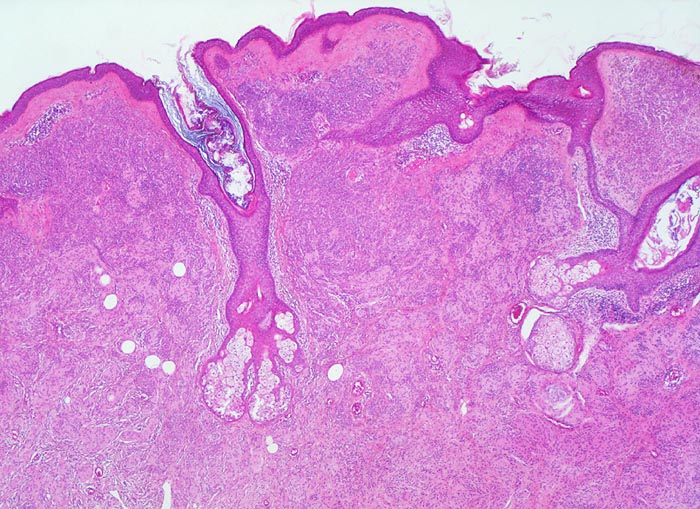

• Symmetrischer leicht exophytischer Tumor.

• Die Tumorzellen bilden Nester in der Epidermis und in der Dermis (=dermoepidermaler bzw. compound Naevus).

Erworbene Naevi können ein lentiginöses oder ein kongenitales Wachstumsmuster aufweisen (Ausbreitung der Naevuszellen in der tieferen Dermis entlang von Adnexstrukturen). Letzteres bedeutet nicht, dass der Naevus bei Geburt schon bestand. Am Anfang der Entwicklung erworbener Naevi steht die Lentigo simplex (> 5299), welche durch Vermehrung einzeln liegender Melanozyten im Bereich der basalen Epidermis zustande kommt und makroskopisch als scharf begrenzte braune Makula imponiert. Daraus entwickeln sich junktionale Naevi mit Nestern von jeweils drei oder mehr Naevuszellen in der basalen Epidermis (> 5362). Bei Compound Naevi (= dermoepidermaler Naevuszellnaevus) finden sich zusätzlich zu den epidermalen auch intradermal gelegene Naevuszellen oder Nester von Naevuszellen (> 565). Compound Naevi zeigen ein sehr variables makroskopisches Bild von gering erhabenen bis zu polypoiden, gestielten oder verrukösen Läsionen. Die Farbe variiert von braun über grau bis zu hautfarben. Diese Naevi bleiben über Jahre weitgehend unverändert und entwickeln sich schliesslich weiter zu rein dermalen (=corialen) Naevi mit ausschliesslich intradermal gelegenen, oftmals unpigmenierten Naevuszellen, um schliesslich vollständig zu verschwinden.